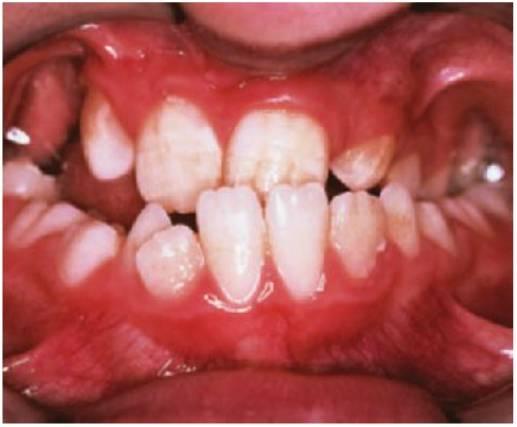

Defectos de desarrollo del esmalte

Además del daño causado por el desplazamiento de los dientes temporales dentro de las criptas de los sucesores permanentes (v. Secuelas de los traumatismos de los dientes temporales más adelante en este capítulo), pueden verse dañados los dientes no erupcionados que se encuentran en la línea de las fracturas de la mandíbula. Los defectos pueden incluir:

- Hipoplasia o hipomineralización del esmalte.

- Dislaceración de la corona y las raíces.

- Desplazamiento del diente en desarrollo dentro del hueso.

- Detención del desarrollo del diente, con obliteración del conducto pulpar.

- Hipoplasia (fig. 7.18E) o hipomineralización (fig. 7.18B) de dientes sucedáneos.

- La dislaceración de la corona o la raíz varía según el estadio de desarrollo (fig. 7.18C, D).